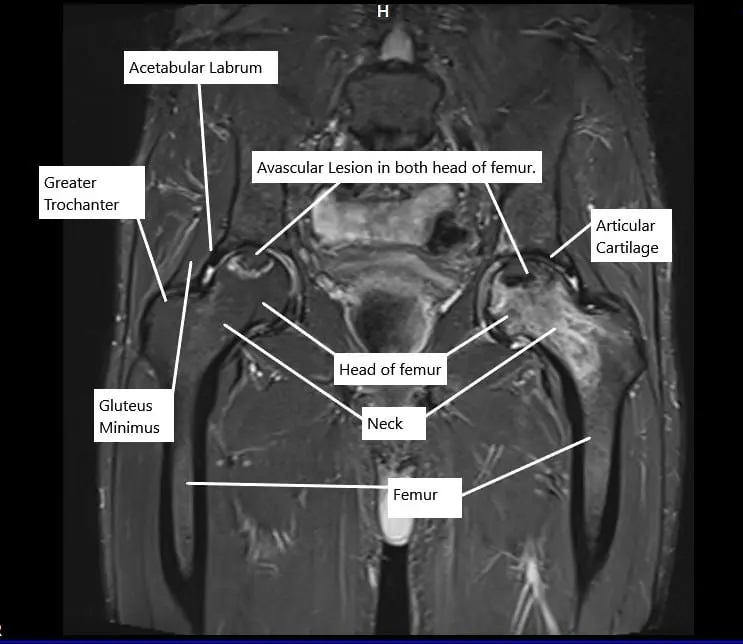

MRI in the coronal section showing avascular necrosis lesions in both hips

In the initial stages of avascular necrosis, there may not be any symptoms and the disease may only be diagnosed on a bone scan or an MRI. With the advancement of the disease, the patient may complain of groin pain that occurs on activity and as well on rest.